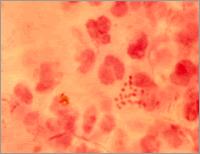

微生物学检查主要是采取尿道脓性分泌物涂片,革兰氏染色镜检,如在中性粒细胞中发现革兰氏阴性双球菌时,就有诊断价值,必要时进行分离培养。对患者应早期用药,彻底治疗。